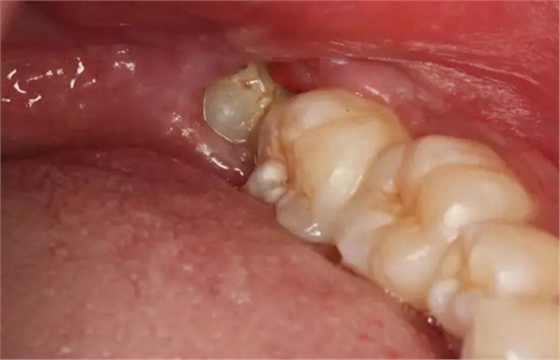

圖2.口外觀:左側(cè)下頜咬肌區(qū)反應(yīng)性水腫、張口困難